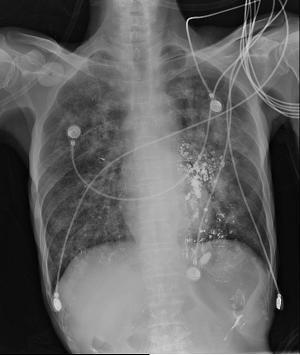

患者白日行钡餐检查,夜间出现呼吸困难,血氧饱和度下降,考虑存在1型呼吸衰竭 讨论: 1.目前针对钡餐误吸性肺炎的治疗措施哪些有意? 2.如何预防本次事件?

男性,61岁吞咽困难1月 进行性吞咽困难,无饮水呛咳,无发热,无咳嗽 咳痰